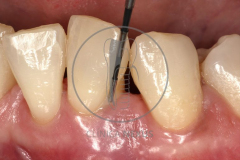

Tratamiento de defectos periodontales infraóseos en sector antero-inferior empleando gel de amelogeninas (Emdogain®) en combinación con un aloinjerto óseo (Biobank®). Paciente de 64 años, sin problemas médicos de relevancia, que presenta una periodontitis leve generalizada, pero asociada a presencia de defectos óseos verticales profundos a nivel de los espacios interdentales entre los caninos y los incisivos laterales inferiores. Tras la pertinente fase higiénica, se llevó a cabo una cirugía periodontal regenerativa, en la que, tras eliminar el cálculo subgingival (factor causal), se empleó una combinación de amelogeninas con un aloinjerto, para promover la regeneración tisular del periodonto perdido. Las imágenes clínicas y radiológicas, al año de seguimiento, reflejan un resultado terapéutico óptimo, con regeneración completa del tejido periodontal y mejora del pronóstico de los dientes involucrados.